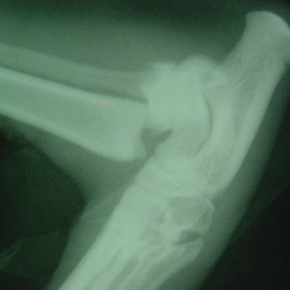

Orthopädie / Gelenkoperationen / Kreuzbandriß

Chirurgie / Bauch- und Brustkorboperationen